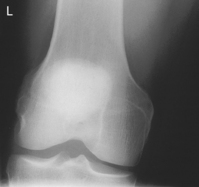

• Prone, knee centered to CR and midline of table or IR

• If patella area is painful, place pad under thigh and leg to prevent direct pressure on patella.

• Rotate anterior knee approximately 5° internally or as needed to place an imaginary line between the epicondyles parallel to the plane of the IR.